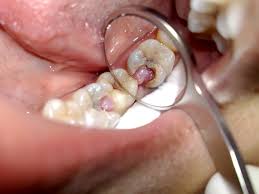

Cavities

Tooth decay is one of the most common reasons that you may have a tooth that is sensitive to cold. In fact, cold sensitivity is one of the earliest symptoms of a cavity. Unlike the previous conditions, cold sensitivity due to a cavity is more localized and is restricted to the involved tooth. See your dentist!